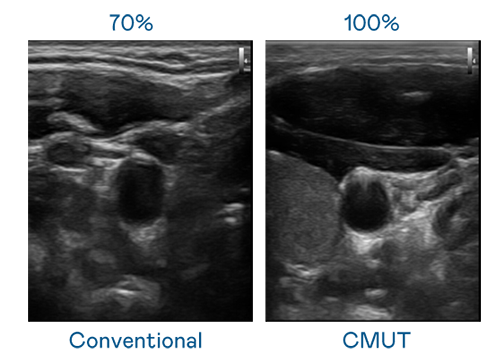

CMUT 技术是一种用电容式微机电元件来产生超音波讯号的技术。与传统 PZT 压电式技术相比,CMUT 频宽增加 30%,更宽频的超音波讯号让影像解析度大幅提升,是实现高影像品质医疗超音波扫描、促进精准医疗发展的关键技术。

超音波影像的解析度高低,首先取决于探头能发出的讯号频宽。w66利来 CMUT 可提供高清晰的超音波讯号,提供高频宽、高灵敏度、影像纹理细节更高的超音波影像,协助医护人员缩短影像判读时间及利用精准的医疗影像进行诊断。